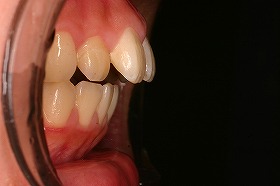

この症例は、出っ歯を矯正治療でキレイにしたケースです。

最初にいらしたときには、出っ歯であることによって

噛み合わせが上手くいかず、口を閉じることが出来ないケースでした。

東京世田谷矯正歯科センターで、治療を進めると

出っ歯も後ろに下がり、噛み合わせもキレイになりました。